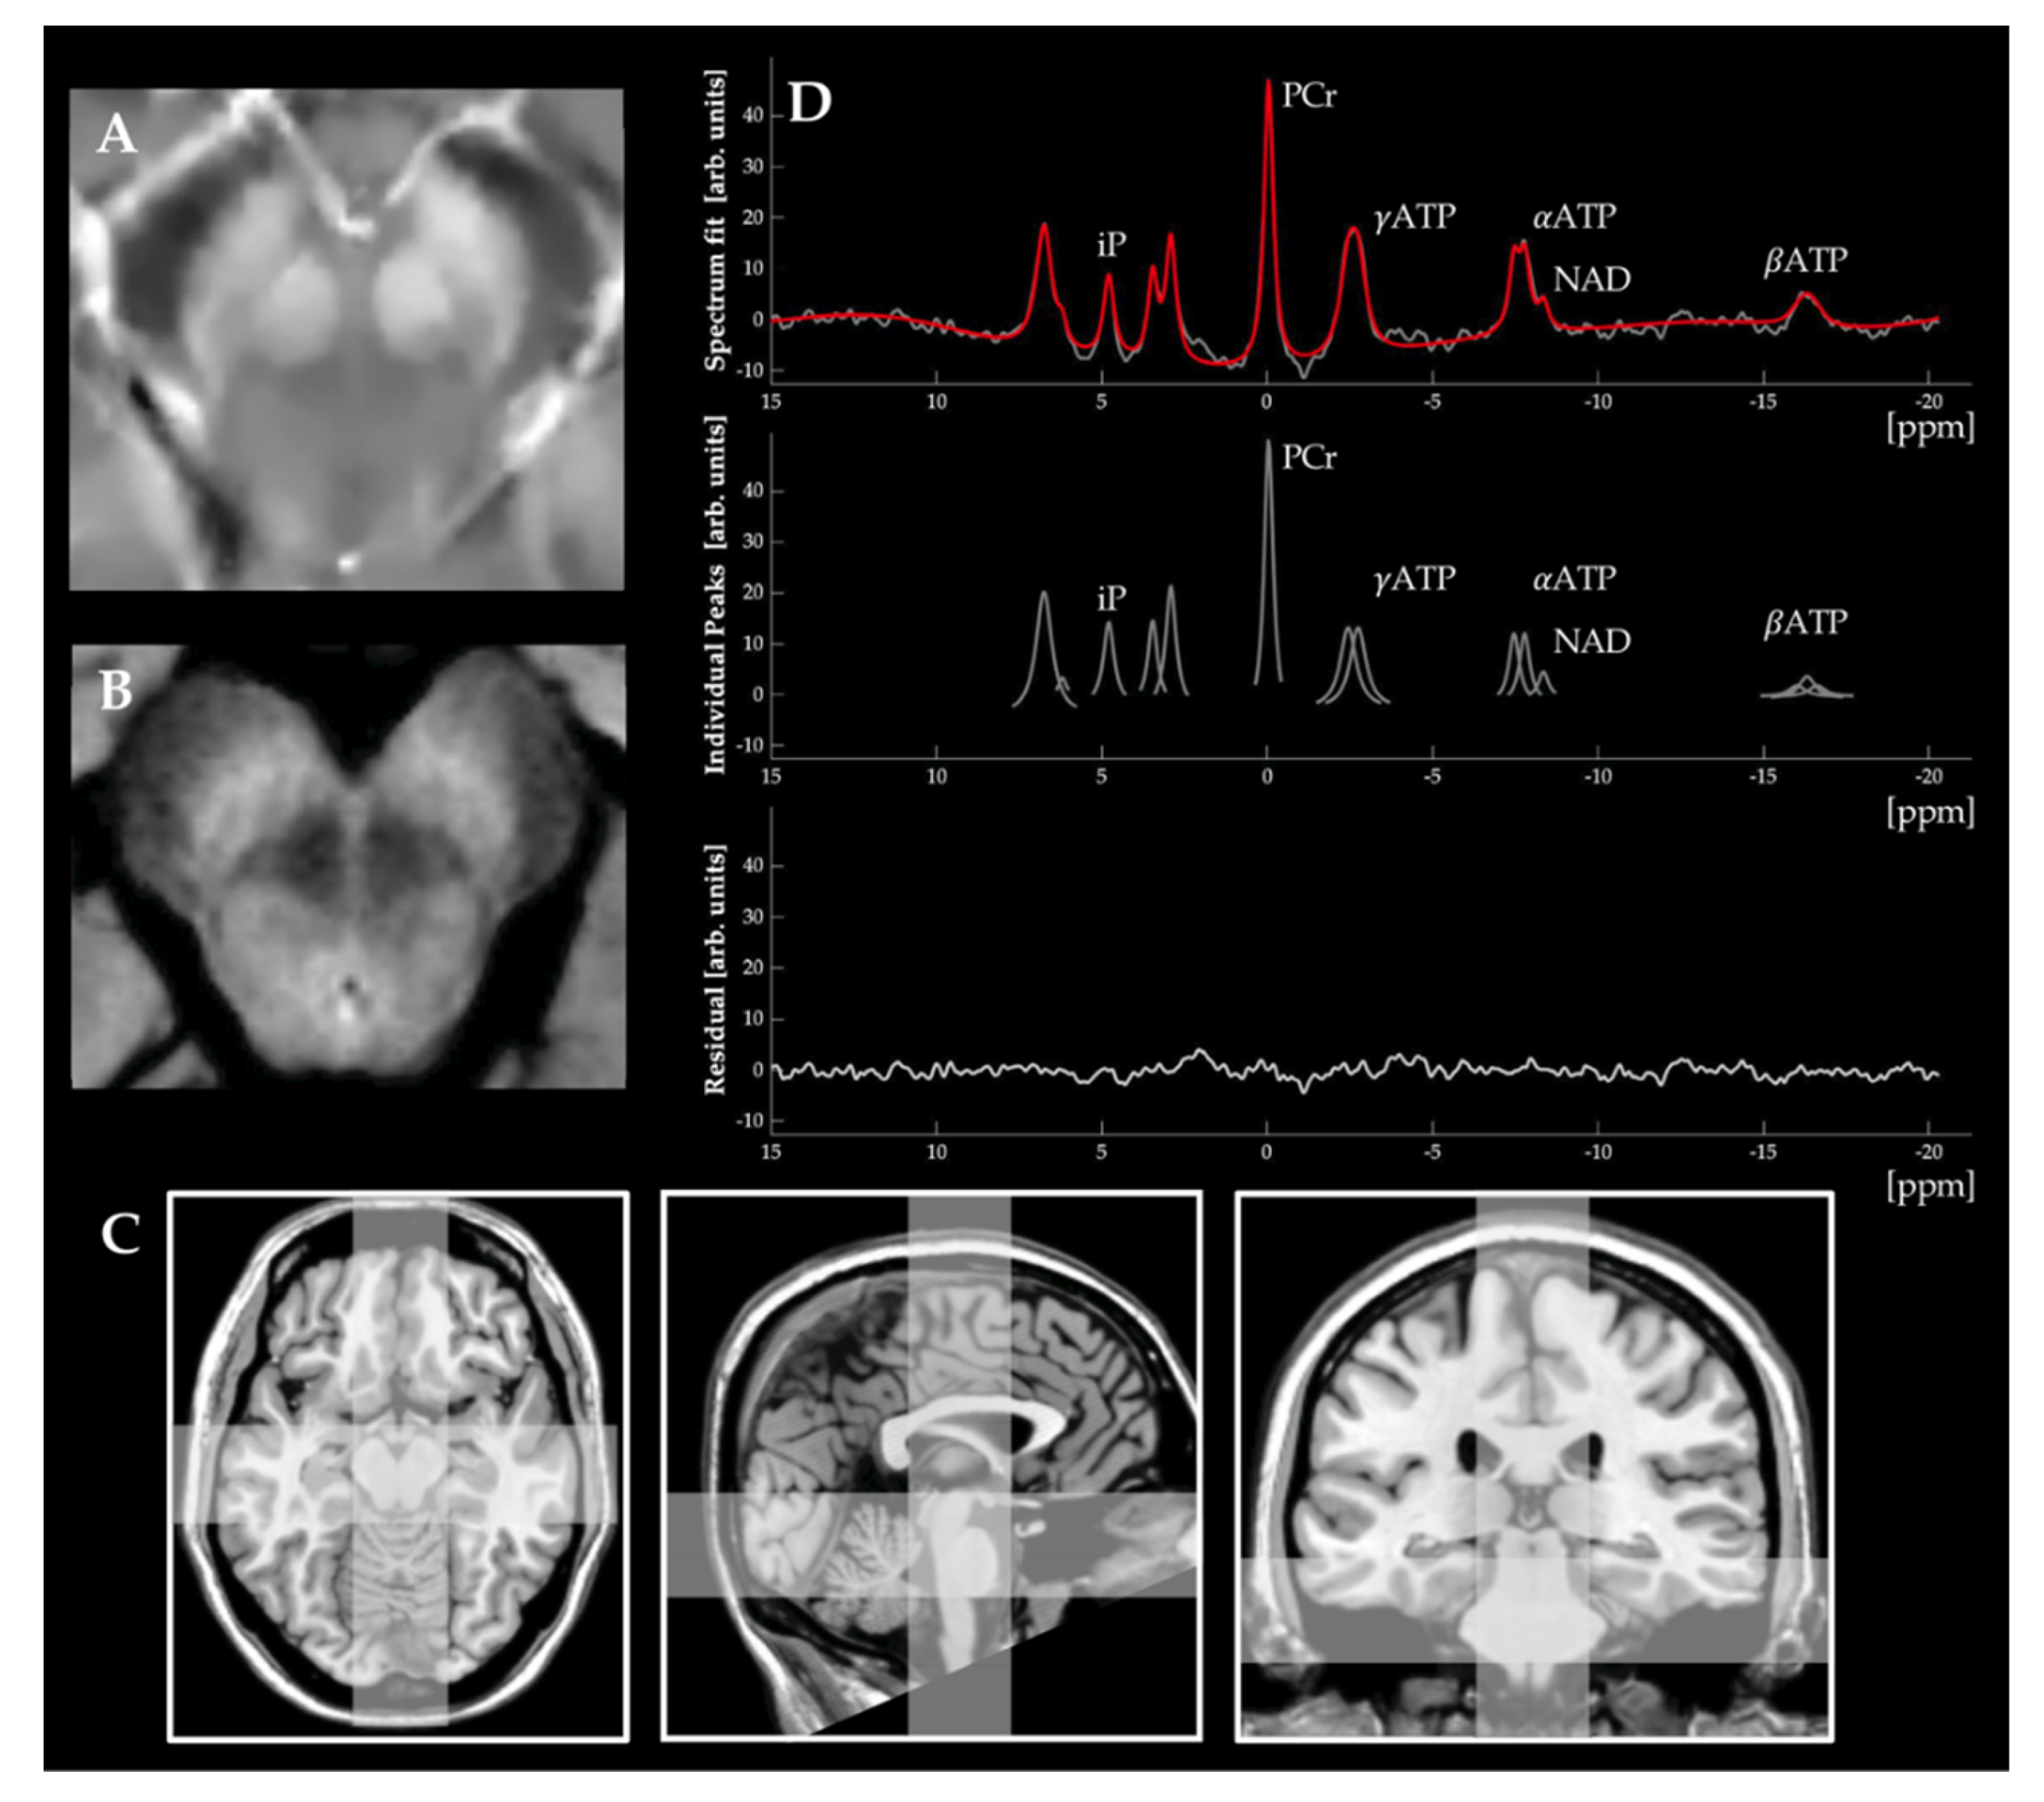

- Buonocore, M.H.; Maddock, R.J. Magnetic resonance spectroscopy of the brain: A review of physical principles and technical methods. Rev. Neurosci. 2015, 26, 609–632. [Google Scholar] [CrossRef]

- Weiduschat, N.; Mao, X.; Beal, M.F.; Nirenberg, M.J.; Shungu, D.C.; Henchcliffe, C. Usefulness of proton and phosphorus MR spectroscopic imaging for early diagnosis of Parkinson’s disease. J. Neuroimaging 2015, 25, 105–110. [Google Scholar] [CrossRef]

- Clifford, B.; Gu, Y.; Liu, Y.; Kim, K.; Huang, S.; Li, Y.; Lam, F.; Liang, Z.P.; Yu, X. High-Resolution Dynamic (31)P-MR Spectroscopic Imaging for Mapping Mitochondrial Function. IEEE Trans. Biomed. Eng. 2020, 67, 2745–2753. [Google Scholar] [CrossRef] [PubMed]

- Kim, S.Y.; Cohen, B.M.; Chen, X.; Lukas, S.E.; Shinn, A.K.; Yuksel, A.C.; Li, T.; Du, F.; Ongur, D. Redox Dysregulation in Schizophrenia Revealed by in vivo NAD+/NADH Measurement. Schizophr. Bull. 2017, 43, 197–204. [Google Scholar] [CrossRef] [PubMed]

- Du, F.; Zhu, X.H.; Qiao, H.; Zhang, X.; Chen, W. Efficient in vivo 31P magnetization transfer approach for noninvasively determining multiple kinetic parameters and metabolic fluxes of ATP metabolism in the human brain. Magn. Reson. Med. 2007, 57, 103–114. [Google Scholar] [CrossRef]